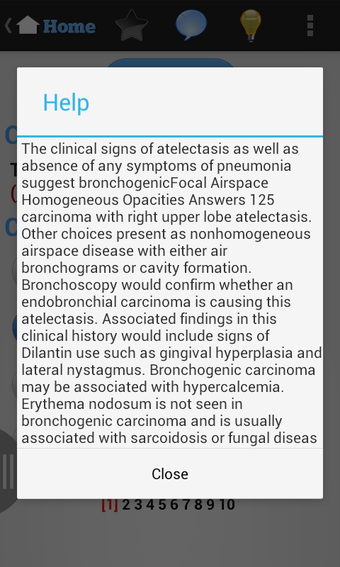

USMLE Exam Prep เป็นแอปพลิเคชัน Android ฟรีที่พัฒนาโดย quizworld ซึ่งเน้นการเตรียมความพร้อมอย่างละเอียดสำหรับการสอบ United States Medical Licensing Examination (USMLE) ให้แก่นักเรียน แอปพลิเคชันนี้ประกอบด้วยภาพพันธุกรรม ไฟล์เสียง และวิดีโอที่ครอบคลุมหลากหลายสาขา เช่น ชีวเคมีและพันธุกรรม รังสีหน้าอก วิธีการคลินิก อายุรศาสตร์ สูติศาสตร์และนรีวิทยา อายุรศาสตร์ประยุกต์ พยาธิวิทยา กุมารเวชศาสตร์ การวินิจฉัยทางกายภาพ ศัลยศาสตร์ จิตเวชศาสตร์ อาการสรีรวิทยา วิธีการคลินิก รังสีหน้าอก และการป้องกันโรค